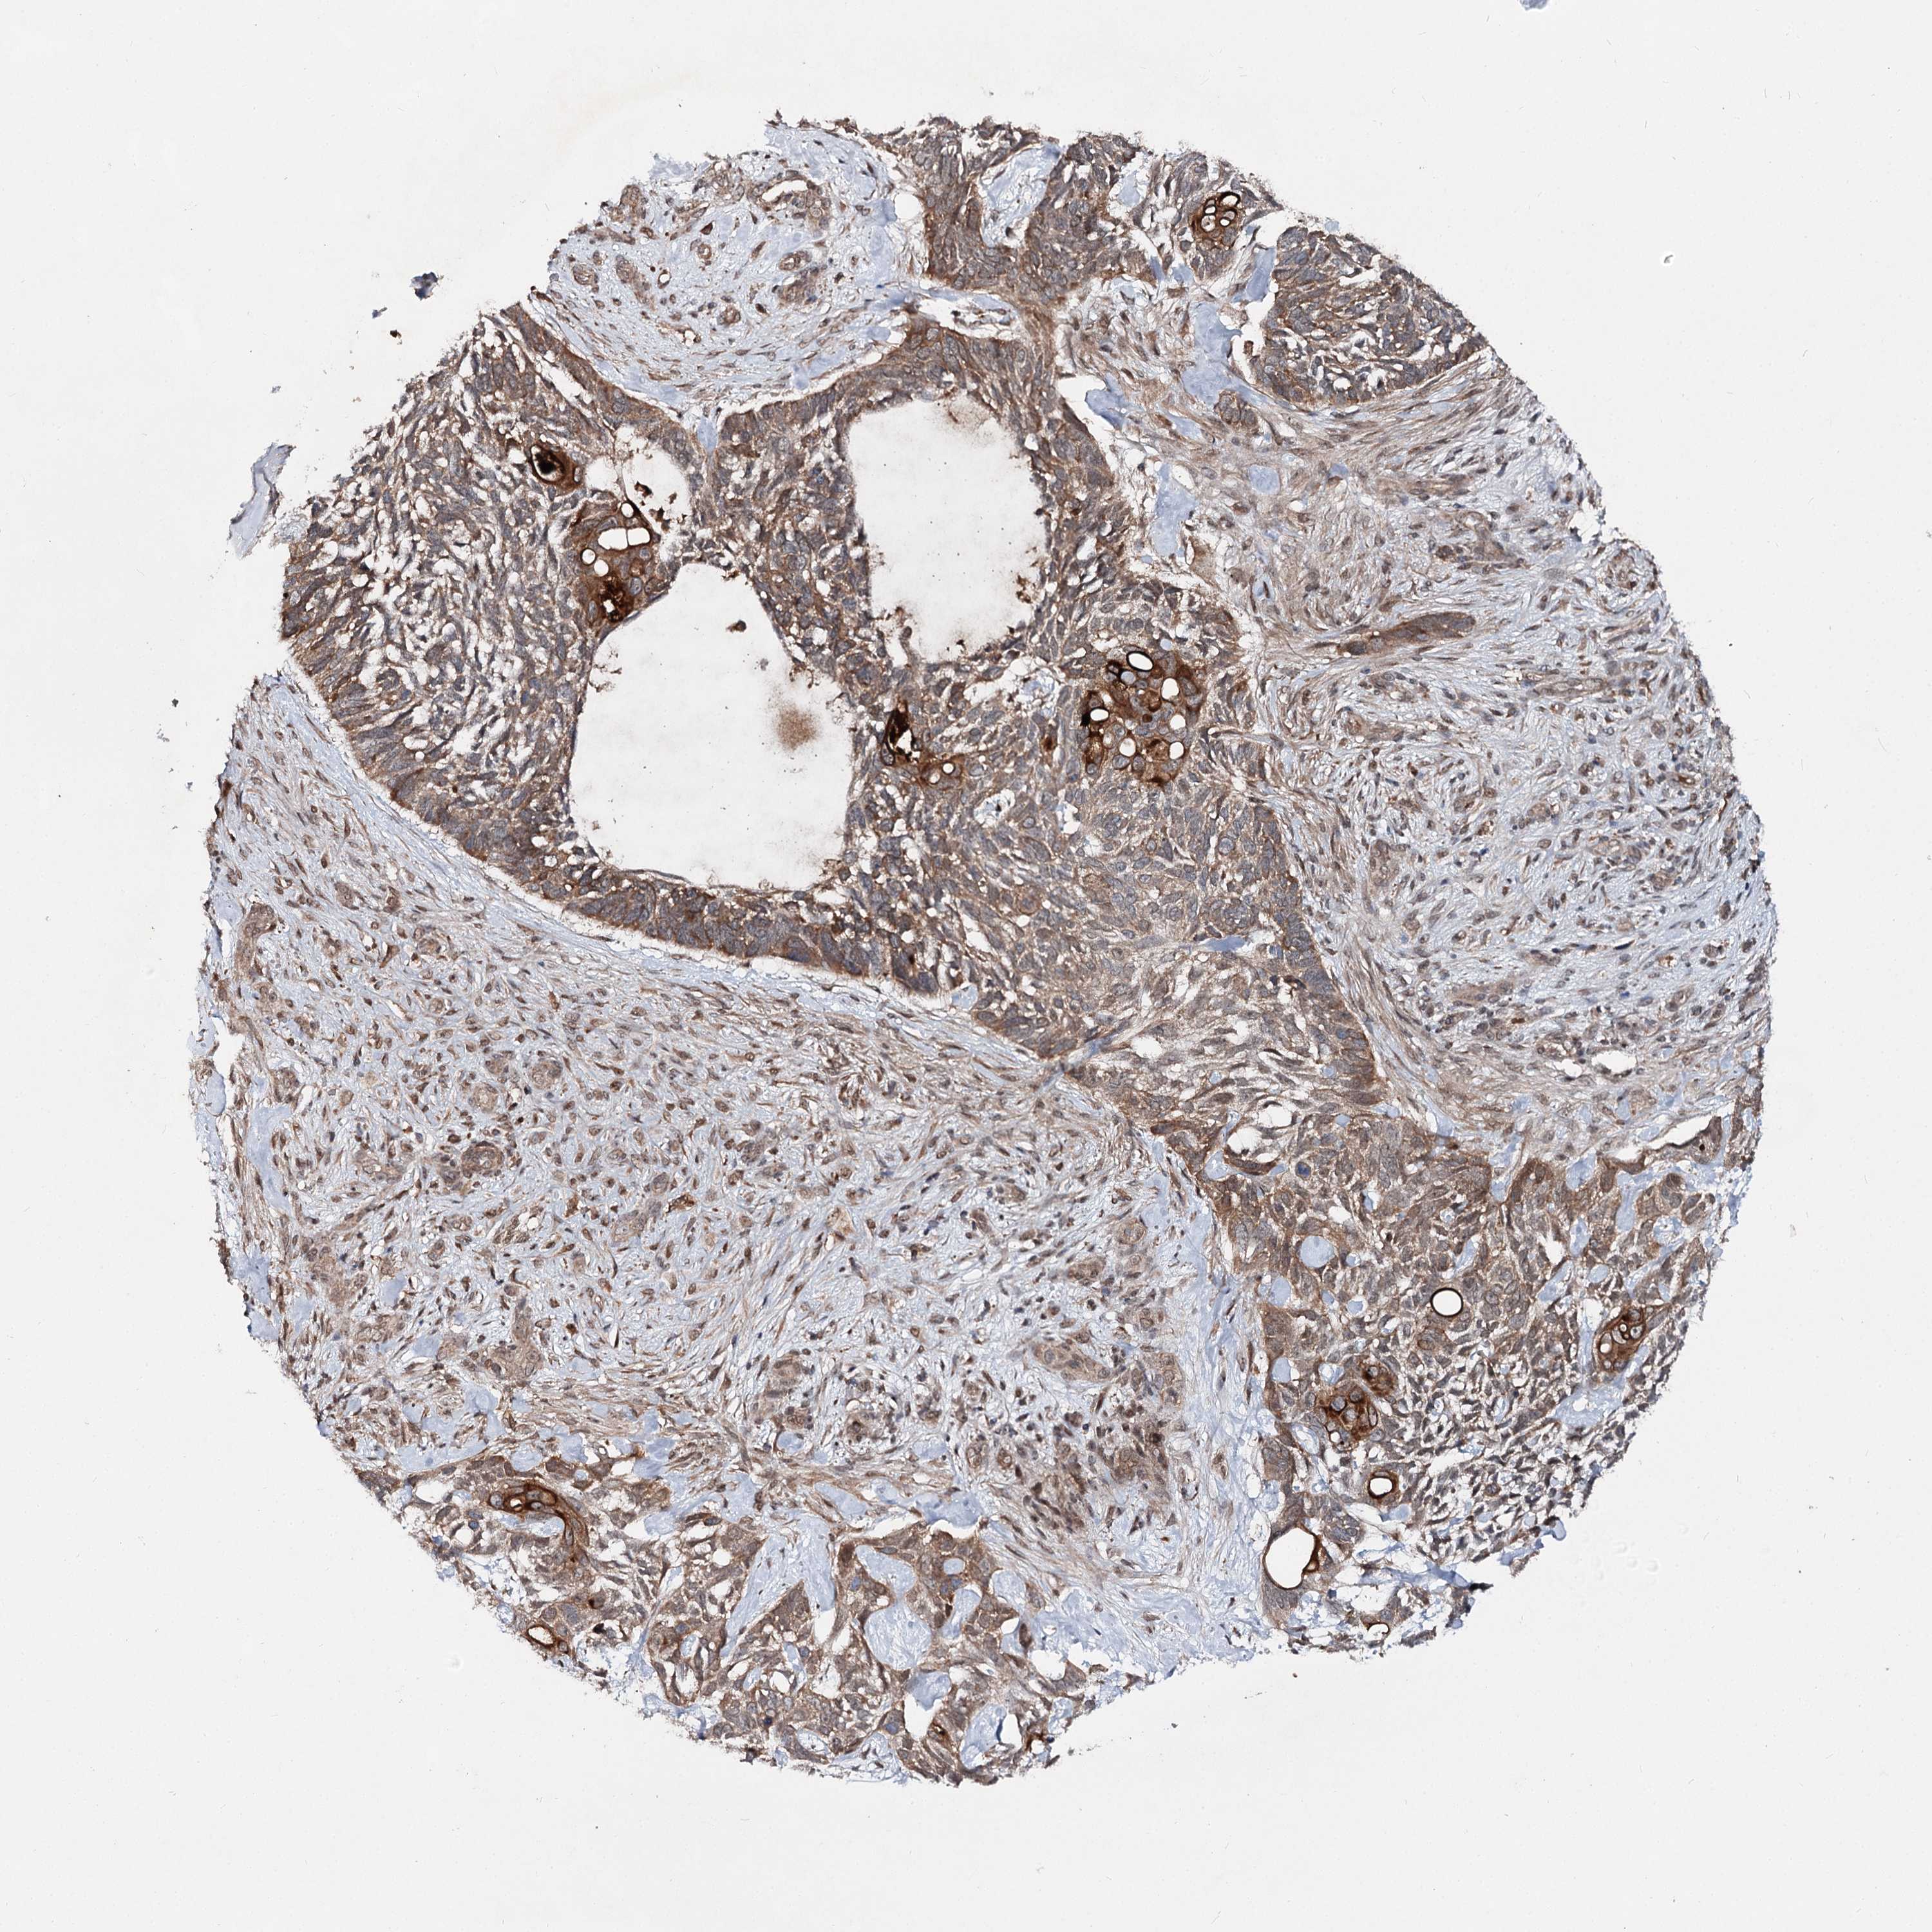

SKIN CANCER - Protein expressioni

A mouse-over function shows sample information and annotation data. Click on an image to view it in a full screen mode. Samples can be filtered based on level of antibody staining by selecting one or several of the following categories: high, medium, low and not detected. The assay and annotation is described here.

Antibody stainingi

Antibody staining in the annotated cell types in the current human tissue is reported as not detected, low, medium, or high, based on conventional immunohistochemistry profiling in selected tissues. This score is based on the combination of the staining intensity and fraction of stained cells.

Each image is clickable and will lead to virtual microscopy that enables deeper exploration of all samples and also displays staining intensity scores, fraction scores and subcellular localization as well as patient and tissue information for each sample.

Antibody HPA038694

Basal cell carcinoma